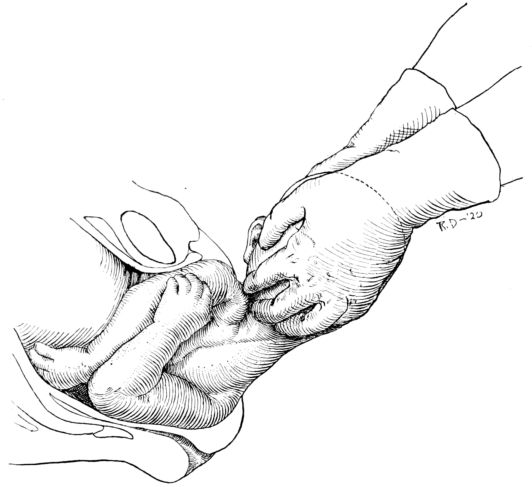

| 70. | Birth of posterior shoulder | 238 |